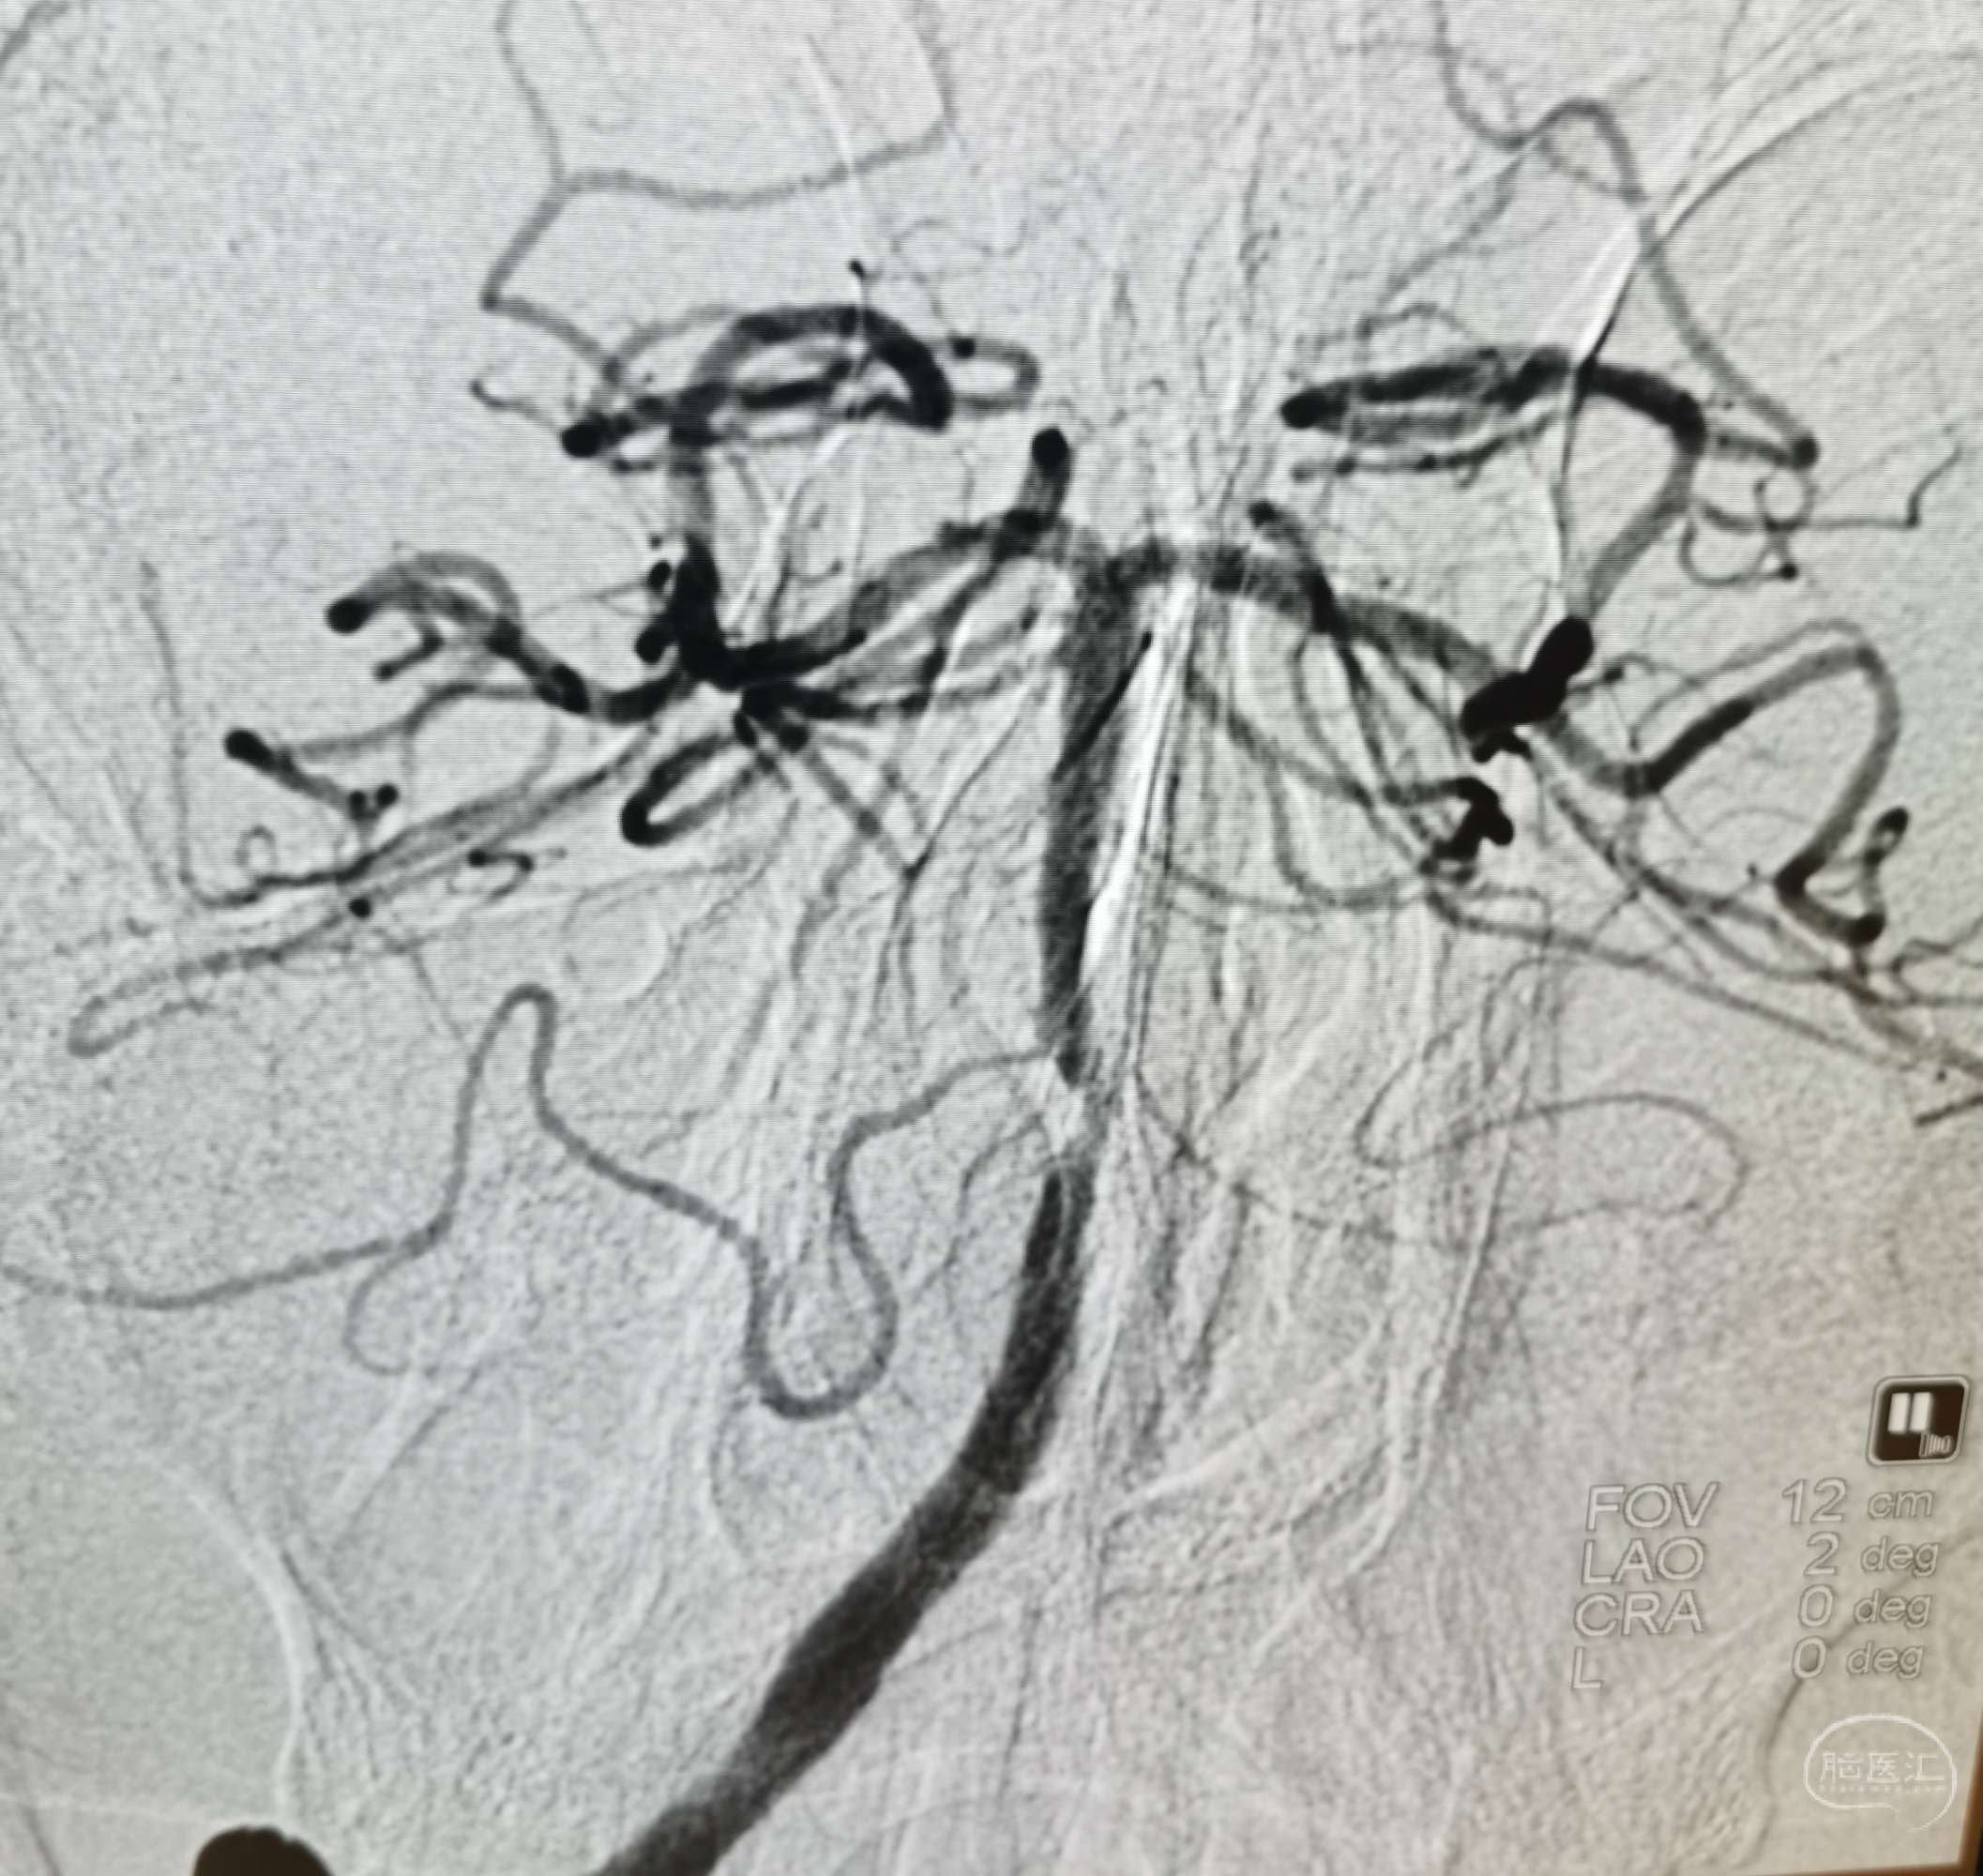

DSA:右侧大脑中动脉、大脑前动脉闭塞,烟雾样血管形成。

DSA:左侧大脑中动脉、大脑前动脉闭塞,烟雾样血管形成。

DSA:右侧大脑中动脉、大脑前动脉闭塞,烟雾样血管形成。

DSA:左侧大脑中动脉、大脑前动脉闭塞,烟雾样血管形成。